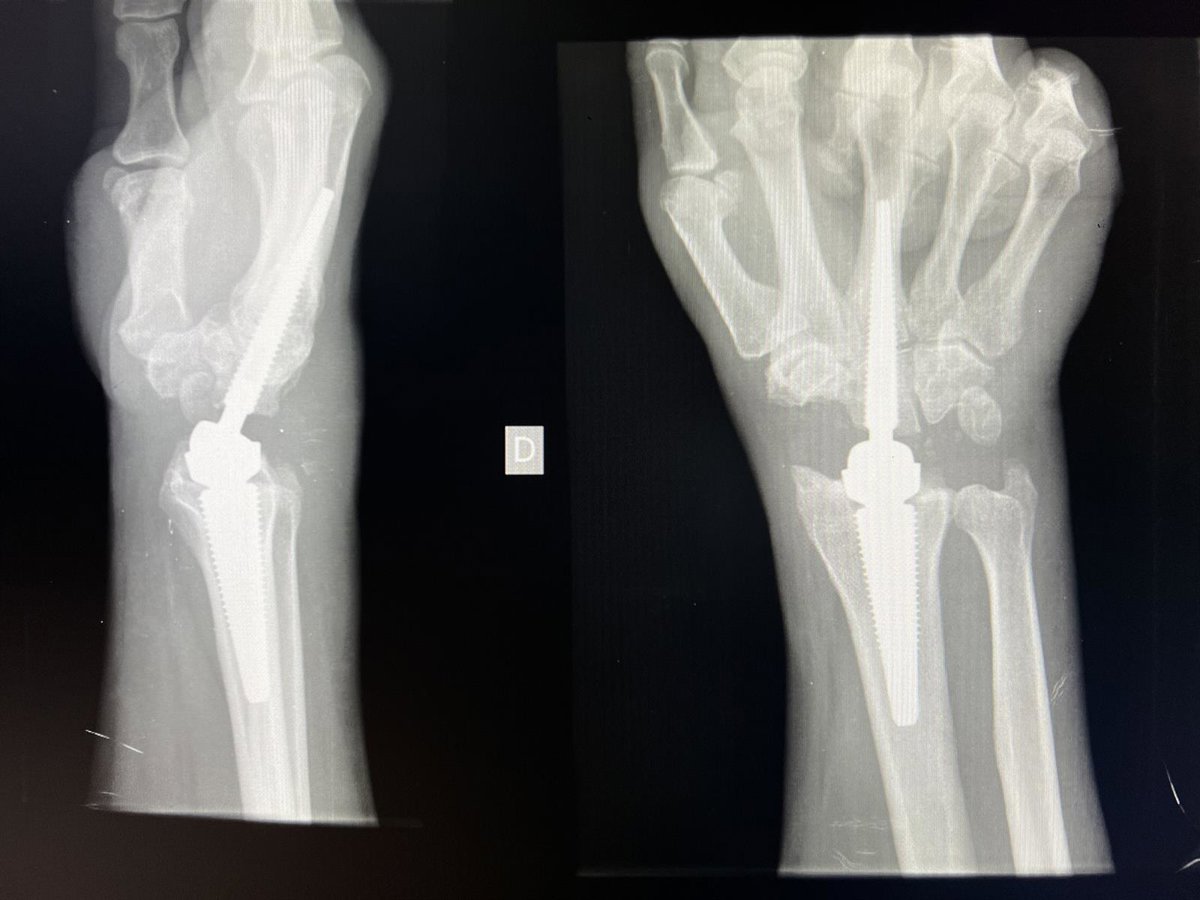

Vithas Madrid Aravaca implanta con éxito una prótesis de muñeca que elimina el dolor y mantiene la movilidad y fuerza

El Hospital Universitario Vithas Madrid Aravaca ha implantado una novedosa prótesis total de muñeca que sustituye a la articulación dañada en diez pacientes que tiene por objetivo eliminar el dolor y recuperar la movilidad y la fuerza.

Esta técnica está destinada a pacientes que sufren patologías como osteoartritis, artritis reumatoide, secuelas de fracturas de radio distal, Enfermedad de Kienbck o fallos en cirugías sobre la muñeca, ha informado Vithas en un comunicado.

Junto al doctor Javier Martínez Mesa, este especialista ha colocado ya diez de estas prótesis totales de muñeca. "Hasta el momento, estamos obteniendo muy buenos resultados. Hay que tener en cuenta que no es un procedimiento que esté indicado con mucha frecuencia y que los pacientes son muy bien seleccionados", ha explicado.